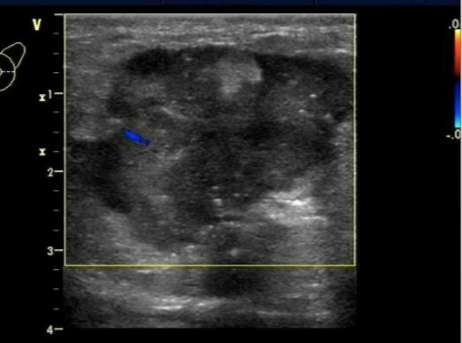

7.乳腺结节的血供。

良性病变多是无血供的实性结节,而恶性结节由于对营养成分的过量摄取,往往其周围的血管数目、血供丰富,往最高血流速度大于20cm/s,血流阻力指数RI≥0.7,这是恶性结节的特征性表现。

结节内血供丰富,是恶性的征象。